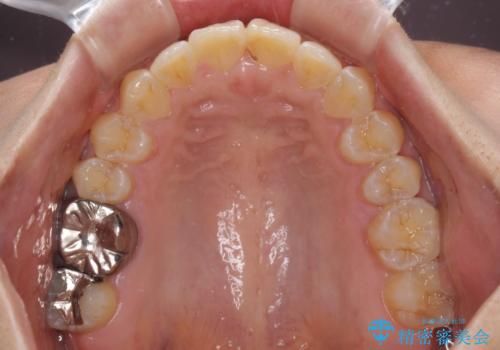

インビザラインによる狭窄歯列の拡大矯正

上下顎ともに歯列全体の後方移動と側方拡大、IPR(歯と歯の間を削る)によってデコボコが解消するように設計し、インビザラインにより治療を行うこととしました。

治療途中で関西に転勤となってしまったため、東京に出張で来るタイミングに合わせて治療を進めることになりました。そのため、治療期間が長くなってしまいましたが、無事に仕上げることができました。